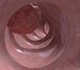

Most colorectal cancer arise from adenomatous polyps. These can be detected and removed during colonoscopy. There are several studies that show that colonoscopy would decrease by > 80% the risk of cancer death, provided it is started by the age of 50, and repeated every 5 or 10 years.

• Colonoscopy every 10 years (currently deemed Gold-Standard of care)